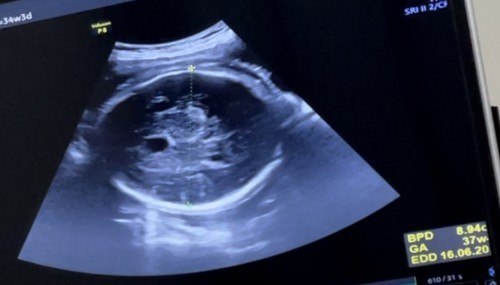

สอบถาม ค่า GA สมอง ตอนนี้น้อง 34 week แล้ว

ก่อหน้า ตรวจค่า ga สมอง น้องปกติ มารอบนี้ คุณหมอบอกสมอง พัฒนาเท่าเด็ก อายุครรภ์ 37week หมดดูละเอียด ไม่มีการ บวมน้ำ อะไรทั้งสิ้น หมอบอกว่าดี ลูกฉลาดแน่ๆ แต่แอบกังวลว่า ตอนคลอด ออกมา สมองลูกจะโตกว่าเด็กปกติไหม ? คุณแม่ทาานใด ตรวจ แล้วค่าเกินมารตฐาน บ้างไหม แล้วคลอดลูกมาแล้ว น้องเป็นยังไงบ้าง ?